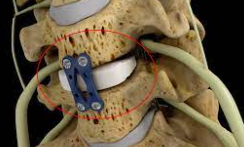

3.1 전방 경추 추간판 절제술 및 융합(ACDF)

이 절차에는 손상된 디스크를 제거하고 인접한 척추뼈를 융합하여 안정성을 제공하고 신경에 대한 압력을 줄입니다. ACDF는 목 디스크 문제에 대한 가장 일반적인 수술 치료법 중 하나이며 통증 및 신경 증상 완화에 높은 성공률을 보입니다.

절차:

외과의는 영향을 받은 경추 디스크에 접근하기 위해 목 앞쪽을 절개합니다. 손상된 디스크를 제거하고 신경이나 척수를 압박하는 뼈 돌기 또는 기타 구조를 제거합니다. 빈 디스크 공간에 스페이서 또는 뼈 이식편을 삽입하여 척추 사이의 올바른 높이를 유지합니다. 금속판과 나사를 사용하여 인접한 척추뼈를 고정하고 시간이 지남에 따라 안정성을 위해 함께 융합합니다.

장점:

통증 및 신경학적 증상 완화에 높은 성공률. 영향을 받는 디스크에 직접 액세스하여 효율적인 압축 해제가 가능합니다.

단점:

유합은 목의 운동 범위를 제한할 수 있으며 잠재적으로 인접한 부분에 스트레스를 증가시켜 시간이 지남에 따라 추가 퇴행을 초래할 수 있습니다.